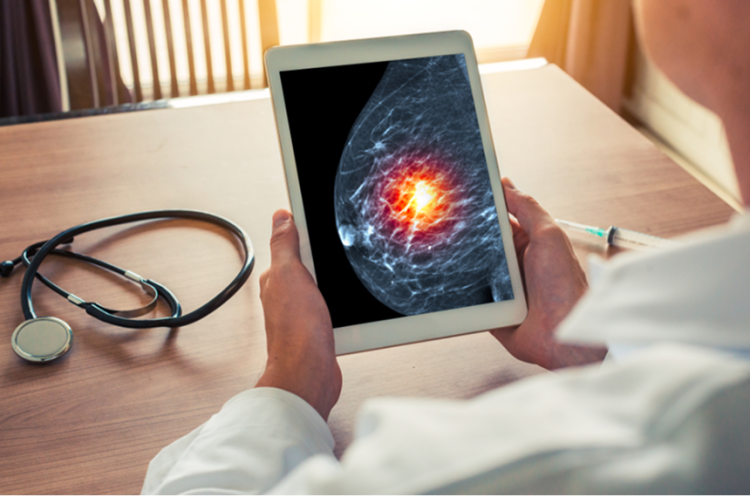

SecondLook® Detection for 2D Mammography

Developed for 2D mammography, SecondLook’s Detection solution automatically marks suspicious lesions, identifying potential cancers and microcalcifications. The solution provides the radiologist with a “second look” which helps detect actionable missed cancers earlier than screening mammography alone, providing workflow enhancements and improved efficiency.